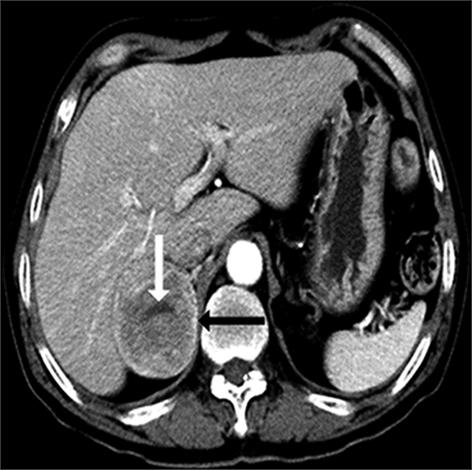

• 嗜铬细胞瘤及副神经节瘤不同生化表型的CT征象对比研究

2024, 49(2):203-209. DOI: 10.13406/j.cnki.cyxb.003433

摘要 (51) HTML (33) PDF 3.10 M (96) 评论 (0) 收藏

摘要:目的 分析生化阴性嗜铬细胞瘤及副神经节瘤(pheochromocytomas and paragangliomas,PPGLs)的电子计算机断层扫描(computed tomography,CT)征象是否有别于生化阳性PPGLs,同时了解生化阳性PPGLs不同表型的CT征象是否存在差异。方法 回顾性分析131例PPGLs患者的术前腹部增强CT图像,包括肿瘤位置、大小、形态、囊变坏死、液-液分层、钙化、向心结节状强化、肿瘤内粗大血管、强化包膜、绝对廓清率及相对廓清率。根据生化水平,将患者分为生化阳性组和阴性组,阳性组进一步分为去甲肾上腺素型、肾上腺素型及多巴胺型。比较各组及各表型间的CT征象差异。结果 相较于生化阴性组,阳性组PPGLs更大(Z=-2.064,P=0.039)、囊变坏死(χ2=6.610,P=0.010)及向心结节状强化(χ2=3.909,P=0.048)的比例更高;相较于去甲肾上腺素型,肾上腺素型PPGLs更大(Z=-2.036,P=0.042)、强化包膜比例更高(χ2=7.242,P=0.007)。结论 肿瘤大小、囊变坏死及向心结节状强化的CT征象有助于术前诊断生化阴性PPGLs,肿瘤大小及强化包膜有助于解释去甲肾上腺素型及肾上腺素型PPGLs不同临床表现产生的机制。